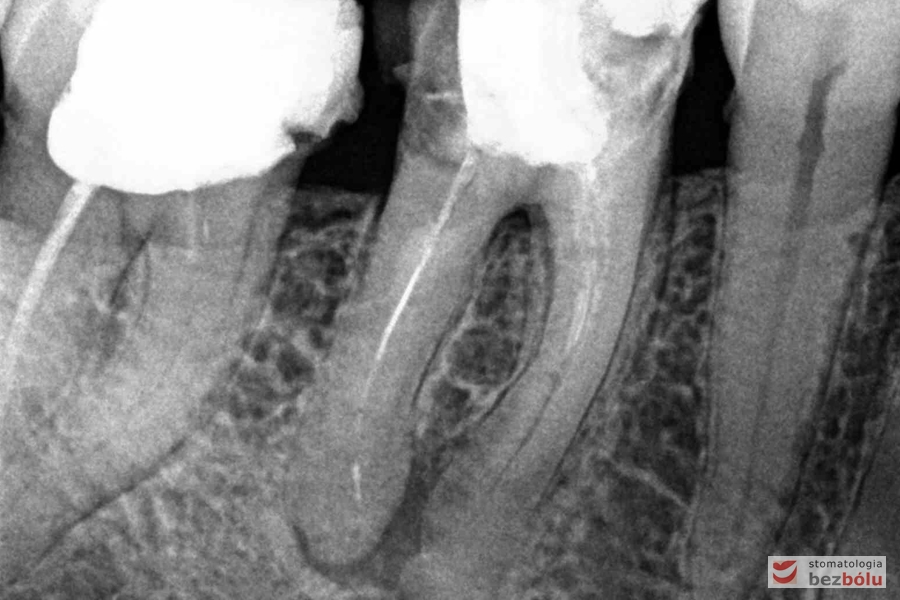

Ocena efektów leczenia kanałowego - szóstka i siódemka górna prawa, kontrola wypełnienia kanałów

Ocena efektów leczenia kanałowego – szóstka i siódemka górna prawa, kontrola wypełnienia kanałów